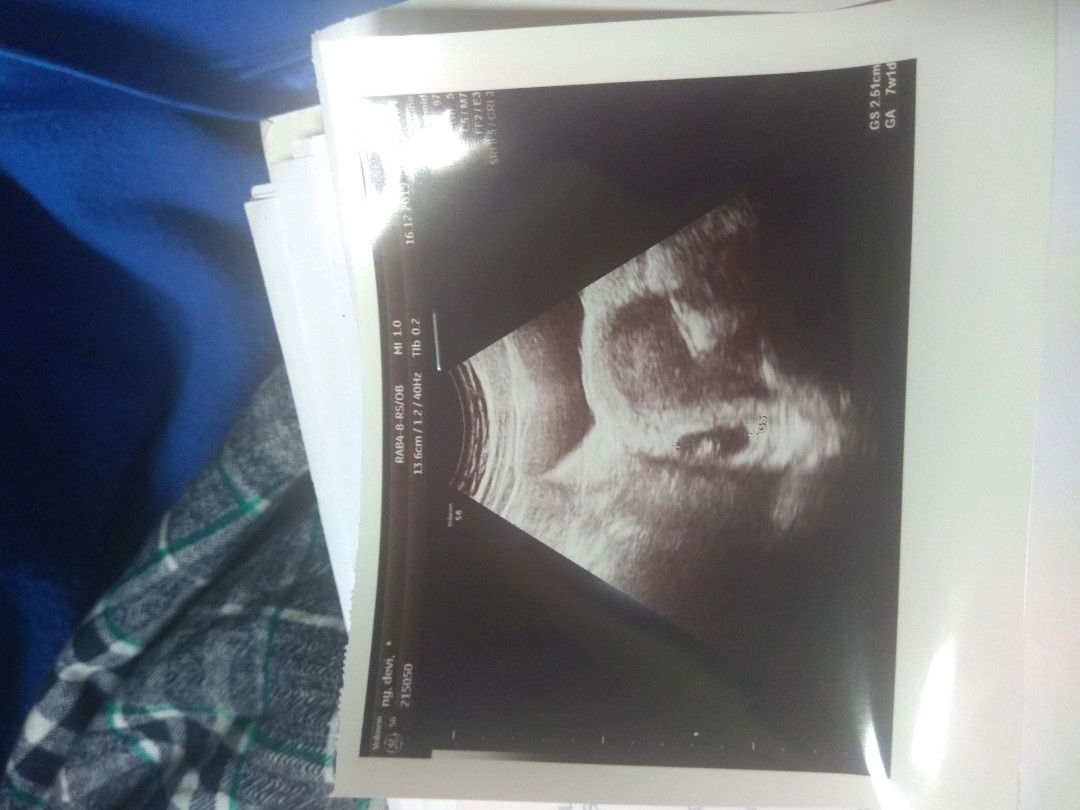

Ibu hamil Anak Pertama

Flek 18 Hari

Halo bun... Saya mau berbagi pengalaman.. Sudah 18 hari mengalami flek bahkan sempet beberapa kali keluar gumpalan darah... Tp alhamdulillah dari usia 4w4d sampe ke 7 week perkembangannya baik... Sempet was was coz flek yang tidak berhenti.. Minta doanya bun agar fleknya behenti dan janinnya sehat sampe melahirkan